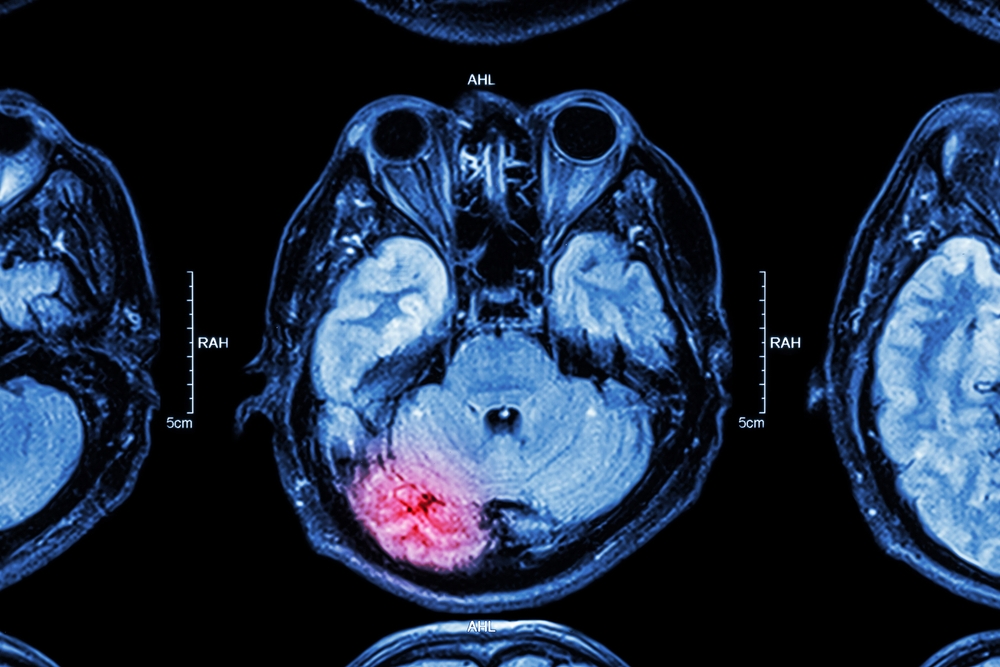

A traumatic brain injury (TBI) occurs when a sudden impact or jolt causes damage to the brain. TBIs can range in severity from mild concussions to more severe injuries that lead to long-term disability or death. Common causes of TBI include:

The symptoms of a TBI vary widely depending on the severity of the injury. Mild TBIs, such as concussions, can result in headaches, dizziness, and temporary confusion. Severe TBIs can lead to more serious consequences, such as memory loss, personality changes, difficulty speaking, and permanent physical or cognitive impairments.